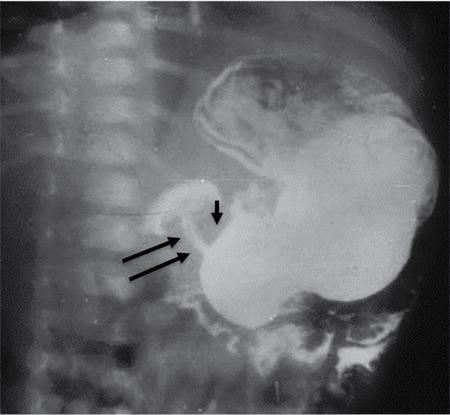

C.V. Kanimozhi, S. Muralinath, Raveendran J. Many of the important congenital gastrointestinal abnormalities present acutely in the newborn; some present much later. These include obstructive gastrointestinal lesions that present with vomiting, abdominal distension and not having passed meconium. The imaging modalities that are most commonly used in the evaluation of neonatal gastrointestinal abnormalities are plain films, contrast studies and ultrasound. Plain films remain a valuable tool in the assessment of abdominal abnormalities in the neonate. They are also an excellent guide to determining the next proper imaging study to perform for a particular problem. Certain neonatal bowel disorders have a pathognomonic appearance on radiographs obviating the need for further imaging. The essential and basic view to be done at the bedside is the supine view of the abdomen. In the evaluation of abnormal intra-abdominal gas patterns, alternative decubitus views, prone and supine cross-table lateral views may be taken. Erect view is not utilized in neonatal practice at the bedside as it is impossible to restrain a neonate in that position and unnecessarily subjects the neonate to stress, which may worsen the condition of an already sick baby. Evaluation of the bowel gas pattern and the anatomic localization of the intra-abdominal gas is the key to diagnosis in the evaluation of diseases of the GI tract. The bowel gas in the neonate is essentially swallowed air (Box 7.8.1). Movement of Air Through the GIT in a Term Neonate Most infants pass meconium by 24 hours of life. In order to interpret the bowel gas pattern and determine if an abnormality is present, it is crucial to know the age of the neonate (hours since birth) at the time the radiograph was taken. When there is impaired swallowing, such as due to CNS depression or in prematurity, radiographs show diminished bowel gas. In cases of bowel atresia, radiographs show absence of bowel gas in distal segments. Thus, the distribution of bowel gas and its pattern serve as pointers to the diagnosis. After the radiograph has been done, depending on the findings, an ultrasound or fluoroscopic contrast study may be performed next. The radiologist should tailor the contrast study to suit the particular patient and the clinical question that needs to be answered. In cases of suspected high GI obstruction, an upper GI contrast series is study of choice; in cases of suspected low GI obstruction a contrast enema should be performed to delineate the anatomy. When performing fluoroscopic studies, it is important to bear in mind the radiation dose and to adopt the ALARA principle. Minimizing radiation exposure in children is important because they are more sensitive to the effects of radiation and have a longer life expectancy than adults. The technical parameters must be adapted to paediatric imaging. Ultrasound is a useful bedside tool particularly in the sick neonate. In neonates, the sonographic image resolution is excellent due to the lack of significant body fat. In neonates, exquisite images of the abdomen can be obtained with the high-resolution ultrasound probe, which permits imaging the bowel wall in great detail. In addition, it can also reveal other causes for abdominal distension or vomiting. In this chapter, we will discuss the aetiology, clinical presentation and imaging appearances of congenital neonatal gastrointestinal abnormalities. We will also discuss common acquired abnormalities that present in the neonatal period, namely necrotizing enterocolitis. Congenital oesophageal malformations of the newborn include the various types of atresia (with and without fistula) and oesophageal duplications. Oesophageal atresia with or without tracheoesophageal fistula (TEF) is a common congenital anomaly that manifests in the neonatal period. It is also the most important congenital malformation of the oesophagus. Oesophageal atresia is commonly associated with other anomalies of the gastrointestinal tract such as imperforate anus, pyloric atresia, duodenal atresia and annular pancreas and less frequently with anomalies of the cardiac and genitourinary systems. About 20% of patients with oesophageal atresia have the VACTERL syndrome (vertebral anomaly, anorectal atresia, cardiac lesion, tracheoesophageal fistula, renal anomaly, limb defect). Oesophageal stenosis and webs may be associated with oesophageal atresia. The aetiology of oesophageal atresia and TEF is not completely understood. Faulty separation of the primitive trachea and oesophagus is the most widely accepted theory. The way the primitive foregut cleaves into a ventral (tracheal) passage and a dorsal (oesophageal) passage is a complex process and is poorly understood. Folds developing from the longitudinal ridge is said to separate the two. When the separation has an extreme tracheal bias, an oesophageal atresia occurs and if the bias is towards the oesophagus, then a tracheal atresia ensues. Incomplete separation may result in fistula of various types. Oesophageal atresia and TEF are classified depending upon the absence or presence and location of the fistula between the oesophagus and the trachea (Fig. 7.8.1). Neonates present within a few hours of birth with excessive salivation, drooling, cyanotic spells and regurgitation of feeds. The inability to successfully pass a nasogastric tube strongly suggests oesophageal atresia. Newborns with H-type fistula may have feeding difficulties and choking, but often the presentation and diagnosis is only later in infancy when the patient presents with cough, choking episodes and recurrent pneumonia. The role of imaging is to diagnose, define the anatomy to the best extent possible and evaluate for other anomalies to provide a clear picture for the paediatric surgeon. For example, it is important for the surgeon to know the side of the aortic arch in order to lateralize the surgical approach. Chest X-ray and Echo can localize the arch and determine if an anomalous right-sided aortic arch is present. Plain films of the chest including abdomen need to be obtained. The radiograph will demonstrate the air-filled distended proximal oesophageal pouch. If a nasogastric tube has been inserted, the coiled tube will be seen within the pouch. Absence of bowel gas in the abdomen indicates oesophageal atresia without a distal fistula – types A and B have this radiographic appearance (Fig. 7.8.2). The presence of gas in the gastrointestinal tract indicates the presence of a distal fistula – types C and D (Fig. 7.8.3). Contrast studies to delineate the proximal pouch are generally not indicated. Coiling of the nasogastric tube in the proximal pouch confirms the diagnosis. Chest radiographs frequently show changes of consolidation due to aspiration pneumonia, most often involving the right upper lobe (Fig. 7.8.4). In cases of H-type fistula, plain films are nonspecific and the diagnosis depends on contrast studies. Radiological diagnosis is made by means of a tube oesophagogram. This study has the potential risk of aspiration and the neonate may desaturate quite rapidly. Hence, it is important to have neonatal emergency resuscitation at hand. The tube oesophagogram is performed under fluoroscopy with the baby in lateral- or steep-prone oblique position. The NG tube is placed at the oesophagogastric junction and is gradually withdrawn while simultaneously injecting contrast. Nonionic low-osmolar contrast agent should be used. Most of the H-type fistulas are located in the lower cervical and upper thoracic regions with the fistula typically coursing upward and forward from the oesophagus. In the presence of a fistula, the contrast will be seen passing into the trachea in an upwardly oblique configuration. Aspiration during the study can also cause the contrast to appear in the tracheal tree and the lungs. It needs to be established whether the contrast has passed through the fistula or whether aspiration has occurred. Recording of the fluoroscopic run and reviewing the images may be required to make this distinction. Repeat examination may be required. Demonstration of H-type fistula can be difficult radiologically. In such patients, bronchoscopy with transfistula guidewire placement has been found to be of use. MRI – High resolution structural MRI is a new technique that is being used to visualize tracheobronchial anatomy. The disadvantage with radiographs is that one cannot determine the anatomic subtype of TEF, the site of the TEF or the length of the gap between the atretic segments. Using ultrashort echotime (UTE) MR imaging, it is possible to visualize the exact site of the fistula and assess the size of the oesophageal gap. This can aid presurgical planning and help identify infants at risk for complications, such as those with a long oesophageal gap. Imaging plays an important role in the evaluation of early and late complications of atresia repair. Early complications include anastomotic leaks and are seen in about 10%–20% of cases. Oesophageal contrast study, using a nonionic low-osmolar contrast agent, is performed to demonstrate the leak at the anastomotic site (Fig. 7.8.5). Leaks are associated with a greater incidence of subsequent stricture development. Anastomotic stricture is a common complication seen in about 30%–40% of cases. Often there is a slight narrowing at the site of repair without the patient having any difficulty in swallowing (Fig. 7.8.6). The anastomotic narrowing is clinically relevant only if the patient has dysphagia; such cases respond to dilatations. Recurrent TEF occurs in 5%–10% of cases after oesophageal atresia repair. Late complications include dysphagia, gastroesophageal reflux, tracheomalacia and chest wall deformities. Dysphagia can occur post-operatively due to abnormal oesophageal motility. Oesophageal dysmotility can be caused by abnormal neural development of the oesophagus or may result from complication of atresia repair. Gastroesophageal reflux affects 40%–65% of patients following oesophageal repair. It may be due to an intrinsic deficiency in the motor function of the oesophagus; this may get exacerbated postrepair due to an alteration of the anatomical gastroesophageal junction. Oesophageal atresia key imaging finding – X-ray shows NG tube coiled in proximal oesophageal pouch. The stomach is divided into the fundus and body proximally and the antrum distally. The antrum is divided by the sulcus intermedius into a proximal pyloric vestibule and a distal pyloric antrum or pyloric canal. This canal terminates into the pyloric sphincter beyond which is the duodenum. Congenital anomalies of the stomach that manifest in the neonatal period are uncommon. Hypertrophic pyloric stenosis (HPS) is the most common surgical cause of vomiting in infants. The incidence is 2–5 per 1000 live births, with geographic and racial variations. Compared to Caucasians, HPS is less common amongst Asian populations. The male to female ratio is approximately 4:1, occurring more commonly in the first-born child. The precise aetiology is unknown. Overactivity or prolonged spasm of the circular muscle of the pyloric antrum is thought to be the primary problem in these infants. This spasm leads to muscle hypertrophy and obstruction. Multiple hypotheses have been proposed for this prolonged spasm. One is that some infants are genetically predisposed to increased gastrin production which leads to a vicious cycle of hyperacidity, increased gastric contraction and secondary development of muscular hypertrophy. Most infants present after the first week of life and before 3–4 months of age. Typical symptoms include projectile nonbilious vomiting, regurgitation and difficulty in feeding. The gastric outlet obstruction can lead to emaciation. The distended stomach with active peristaltic activity may be visible through the thin abdominal wall. In the past barium upper GI series was the mainstay diagnostic tool for HPS. Prior to the barium study, the stomach may need to be decompressed via a nasogastric tube. The classic sign on a barium study is the ‘string sign’ (Fig. 7.8.7) produced by a thin stream of barium in an elongated narrowed pyloric canal; the canal typically curves upward. In severe cases, complete obstruction will lead to the ‘beak sign’, which is produced by beaking of the contrast as it enters the pyloric canal. With lesser degrees of obstruction, the ‘double track sign’ is seen. This is produced when the pyloric canal is flattened and the barium accumulates in the crevices along either side of the flattened canal. Pylorospasm can transiently mimic the findings of HPS. Currently, ultrasound is the modality of choice for the diagnosis of HPS and upper GI studies are seldom used. Ultrasound is considered the ‘gold standard’ as it allows direct examination of the pyloric muscle and also provides the ability to perform a dynamic study. The ultrasound examination is performed with a linear high-frequency transducer (6–10 MHz). The examination begins with the baby in supine position. First, the antropyloric region is identified; the pylorus is usually located medial and posterior to the gall bladder. The normal pyloric muscle is a thin hypoechoic layer that measures 2 mm or less. The abnormal pyloric canal shows thickening of the muscle and the mucosa to varying degrees. In cross section, it is seen as a hypoechoic structure likened to a doughnut. The length of the canal is measured in long section where its appearance is likened to the cervix. The sonographic diagnostic criteria for HPS are a thickened muscle layer measuring ≥3 mm and an elongated pyloric channel ≥15 mm (Fig. 7.8.8). The diameter of the pylorus in cross section was also one of the originally used measurements. However, due to a significant overlap between normal and abnormal, this measurement is no longer utilized. Additional ultrasound findings of HPS are hypertrophy of the pyloric mucosa and a distended, actively peristalsing stomach. The hypertrophied redundant mucosa projects into the antrum analogous to the ‘nipple sign’ in barium studies (Fig. 7.8.8D.). Colour Doppler imaging shows increased flow in the muscle and mucosa. The above-described measurements of pyloric muscle thickness and canal length are vital to diagnosis. However, dynamic assessment is equally important. One must evaluate the antropyloric region over a period of time to ensure persistent stenosis without evidence of relaxation and opening of the canal. A distensible antropyloric region with normal passage of gastric contents excludes HPS. Transient contractions of the pylorus or pylorospasm can mimic pyloric stenosis in both measurement and appearance. With observation over a period of time, opening of the pyloric canal may be visualized. Hence the key to diagnosis of HPS is persistent non-relaxing thickened musculature. Gas in the stomach may obscure the pylorus. To avoid this, place the infant in an oblique position, right side down which will allow the antrum to fill with fluid. Conversely, an overdistended fluid-filled stomach can displace the pylorus dorsally. In such cases, turning the infant left side down will displace the fluid towards the fundus and will allow the pylorus to rise to a more anterior position. At times, equivocal examinations may occur where the muscle measures 2–3 mm in thickness and does not relax. In these patients, careful monitoring with repeat ultrasound is warranted. In a few cases, the abnormalities advance overtime to fully developed HPS. Hence in such equivocal cases if vomiting continues, follow-up ultrasound is advisable. Surgical pyloromyotomy is the treatment for HPS. On ultrasound, the myotomy site can be seen as an interruption in the hypoechoic doughnut. It is important to be aware that postsurgery, the pyloric muscle may remain thickened for up to 5 months with a gradual return to normal thickness. In the first week after surgery, the muscle can be the same thickness as pre-op or even thicker. One should not be alarmed by this appearance. The dimensions gradually return to normal over the course of a few months. Postop if the child is thriving well, there is no need for imaging to be performed. HPS key imaging finding: On high-frequency ultrasound muscle thickness ≥3 mm and elongated pyloric channel ≥15 mm. Pyloric atresia is a rare anomaly comprising less than 1% of all intestinal atresias. Pyloric atresia is classified into three types (Fig. 7.8.9): The exact aetiology remains controversial. In the past, it was postulated that failure of recanalization of the gastrointestinal tract was the cause. Recent evidence suggests that pyloric atresia is the result of localized vascular occlusion. This vascular theory suggests that the atresia is due to focal ischemia secondary to intrauterine stress, vascular insult or anoxia. In complete obstruction, the presentation is in the neonatal period with nonbilious vomiting within the first few hours of life. Incomplete obstruction due to a diaphragm has a variable presentation depending on the size of the orifice. These patients can present later in life with intermittent vomiting or postprandial vomiting. In complete pyloric atresia, a dilated stomach is present on radiographs with absence of gas in the distal bowel. This is known as ‘single bubble’ appearance (Fig. 7.8.10). This appearance is diagnostic and in such cases, contrast studies are generally not required. In the membranous type, there is an opening in the centre of the diaphragm and hence, the obstruction is usually incomplete. On radiographs, the stomach is distended and lesser than normal volumes of air is present in the small bowel (Fig. 7.8.11). On upper GI barium studies, a diaphragm is seen as a thin (2–4 mm) linear filling defect that spans across the antrum with a normal pyloric canal. One needs to determine on fluoroscopy whether the membrane is causing significant obstruction or not. If obstructing, the diaphragm will balloon out with gastric peristalsis. In incompletely obstructing diaphragms, the edges of the diaphragm will be visible but there will no obstruction or ballooning. Pyloric atresia key imaging finding: X-ray abdomen – ‘single bubble’ appearance. Microgastria is an extremely rare congenital abnormality wherein the stomach is small, midline in position and typically associated with a dilated oesophagus. The stomach is represented by a small tubular structure without recognizable differentiation into fundus, body, antrum and pylorus. Agastria is the most extreme form of microgastria. Microgastria is frequently associated with other anomalies such as polysplenia-asplenia syndrome, malrotation, gastrointestinal atresia and vertebral, cardiac, renal and limb reduction anomalies (VACTREL association). Microgastria occurs due to arrest in early development of the foregut. In the 5th week of gestation, dilatation of the region of the future stomach occurs. Ninety-degree rotation of the stomach occurs in the 6th week, followed by development of the greater and lesser curves and growth of the fundus in the subsequent weeks. Arrest of this process leads to microgastria, with severity dependent on the stage at which arrest occurs. The development of spleen within the dorsal mesogastrium of stomach explains the association of microgastria and splenic anomalies. The association of limb, cardiac, tracheoesophageal, vertebral and renal anomalies has been attributed to impairment of early mesodermal development. The symptoms are related to the effects of the inadequate stomach and dilated oesophagus or due to the associated severe anomalies. These babies may present with feeding difficulties, failure to thrive, vomiting, recurrent aspiration and malnutrition due to severe gastroesophageal reflux. Radiographs may show an absent stomach bubble; in some cases, the shadow of the dilated oesophagus may be seen in the lower chest. On an upper GI study, the stomach appears small, tubular and midline in position. There is often associated severe gastroesophageal reflux and a very dilated oesophagus. The oesophagus dilates to take over the storage function of the inadequate stomach. Additional imaging studies are required to identify the associated anomalies. Key imaging finding: Upper GI study – Small, tubular stomach located in the midline. Congenital anomalies of the duodenum present with obstructive symptoms. The primary considerations for bilious vomiting in the neonate are duodenal atresia, duodenal stenosis, annular pancreas and malrotation with midgut volvulus. The most important investigation in the majority of these patients is an upper GI series as it accurately demonstrates the level and nature of duodenal obstruction. Duodenal atresia may be seen in isolation or in the setting of trisomy 21 (about 30% of patients have Down’s syndrome). Associated anomalies are frequent and include malrotation, oesophageal atresia, annular pancreas, biliary atresia, congenital heart disease and vertebral anomalies. Duodenal atresia is due to failure of gut recanalization during embryologic development leading to complete obstruction. Normal recanalization of the duodenum occurs between the 9th and 12th weeks of gestation. Failure of this process results in duodenal atresia. In most cases (roughly 80%), the atresia is distal to the ampulla of Vater. Neonates with duodenal atresia present with bilious vomiting in the first few hours of life. In those patients where the atresia is proximal to the ampulla, the vomitus will be nonbilious. In duodenal atresia, air is present in the stomach and duodenum with no gas in the distal intestinal tract. Dilatation of the stomach and the duodenum produces the characteristic ‘double bubble’ appearance on radiographs (Fig. 7.8.12). This appearance is diagnostic and rarely requires further imaging. Key imaging finding: X-ray abdomen – ‘double bubble’ appearance Duodenal stenosis and duodenal web cause partial obstruction due to a narrowed segment or thin membrane, respectively. As with duodenal atresia, both these conditions show a strong association with malrotation, annular pancreas and a preduodenal portal vein. Duodenal web and stenosis is due to incomplete recanalization of typically the second part of the duodenum. In babies with duodenal stenosis, the presentation and clinical findings depend on the degree of stenosis. Those with less severe forms of stenosis may present later in life. Radiographs in duodenal stenosis and web show a distended stomach and duodenum. Since the obstruction is incomplete, gas will be present in the distal loops. On upper GI study, duodenal stenosis is seen as a focal narrowing in the second part of the duodenum (Fig. 7.8.13). In duodenal web, a thin membrane/diaphragm is seen that partially obstructs the lumen, usually in the second segment of duodenum. The membrane is often difficult to demonstrate (Fig. 7.8.14). A ‘windsock deformity’ may also be seen; this appears as a proximal dilated duodenal segment with contrast outlining a thin web that bulges into a distal nondilated segment. This windsock duodenum is seldom seen in the neonatal period as this appearance is due to stretching of the membrane over time. Key imaging finding: Upper GI study – narrowing in second part of duodenum. Annular pancreas is an anomalous band of pancreatic tissue that encircles the second portion of duodenum. Annular pancreas may result in extrinsic duodenal obstruction. Often there is associated intrinsic duodenal abnormality viz. some degree of duodenal atresia, web or stenosis. As in duodenal atresia, associated anomalies such as trisomy 21, cardiac defects, malrotation, oesophageal atresia and anal atresia can occur. The pancreas arises as two endodermal outgrowths, ventral and dorsal buds, from the duodenum. The head of the pancreas derives from the smaller ventral bud. Annular pancreas occurs if the ventral bud becomes tethered to the duodenum or it fails to rotate completely before fusion with the dorsal bud. The clinical presentation is similar to duodenal atresia or stenosis. If the obstruction is complete, presentation is in the neonatal period with bilious vomiting. Cases of incomplete obstruction may remain asymptomatic until adulthood. Annular pancreas is the second most common condition to produce a ‘double bubble’ appearance on radiographs. Plain films will show dilatation of the stomach and duodenum. Upper GI contrast study will show narrowing of the second part of duodenum (Fig. 7.8.15). On ultrasound pancreatic tissue may be seen encircling the second part of duodenum (Fig. 7.8.16). At times the appearance may resemble a mass at the level of head of pancreas.